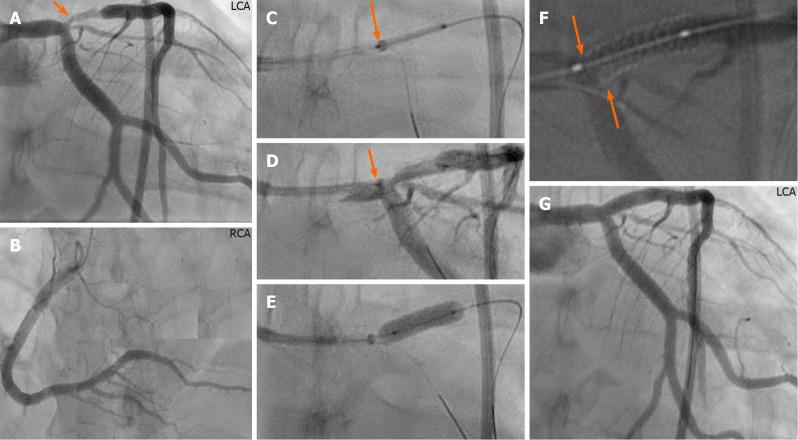

A challenging technical scenario frequently encountered in a percutaneous coronary intervention of a coronary bifurcation lesion (CBL) is stent implantation of only the stenosed segment without compromising the other two normal segments in non-true bifurcation lesions. Another is precise stent implantation covering the side branch ostium without leaving excessive stent metal at the other two segments of a bifurcation lesion in complex true bifurcation lesions. The aim of this study was to describe a novel stenting technique for both non-true and true CBLs by using a guide extension catheter (GuideLiner). With the assistance of a guide extension catheter mounted on both the main and the side-branch guidewires and with its intubation down to the bifurcation carina, a stent can be implanted in the side branch segment or distal main segment of the bifurcation lesion appropriately without compromising the other two segments of the coronary bifurcation. Stent implantation is described in three bifurcation lesions in three cases and shown in detail with illustrative figures. The technique facilitates side-branch only stenting in side-branch mono-ostial (medina 0, 0, 1) CBL or only the distal main segment in distal mono-ostial (medina 0, 1, 0) CBL without compromising the other two remaining segments when using the one-stent technique in non-true CBLs without leaving unnecessary excessive stent metal at the bifurcation site and when using a two-stent technique in complex true bifurcation lesions (tri-ostial or medina 1, 1, 1). Consequently, through optimizing stent deployment, the technique may have the potential to reduce the risk of subacute stent thrombosis and future in-stent restenosis. The most appropriate lesions suitable for the technique, and some other practical tips are also described.